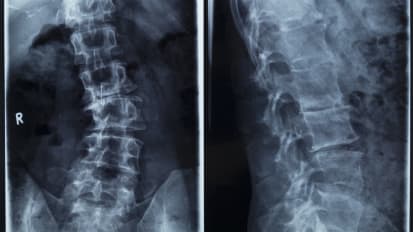

Emory Spinal Fusion Patients Recover Faster with O-Arm™ Surgical Imaging

The world-renowned spine surgeons at Emory Orthopaedics & Spine Center have been perfecting minimally-invasive spinal fusion techniques with O-Arm surgical imaging (a 3D navigation tool) for several years. Patients suffering from lumbar ...

Shatter the Myth: Treatment Options Do Exist for Adults Suffering from Scoliosis

Every week, the surgical team at Emory Orthopaedics & Spine Center meets to discuss complex cases. They collaborate with other world-class specialists within the Emory Healthcare system and develop individualized treatment plans for adults ...